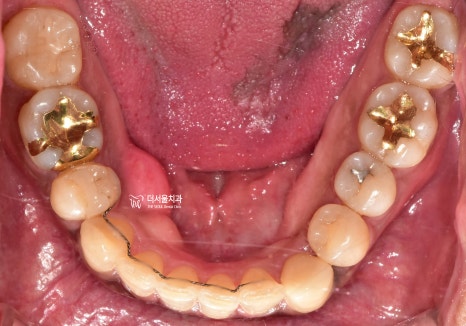

그러면서 하악에서도,

치열의 불규칙성이 같이 관찰되는데

결국 이런 치열들 때문에,

발치를 결정할 수 밖에 없었고

양측으로 동시에 발치를 하는게 아닌,

#14, 44번 치아만 발치하는

편측발치로 진행을 하게 될 상황입니다.

편측 발치를 해야 되는 이유는,

아래 사진 2장에서 보실 수 있습니다.